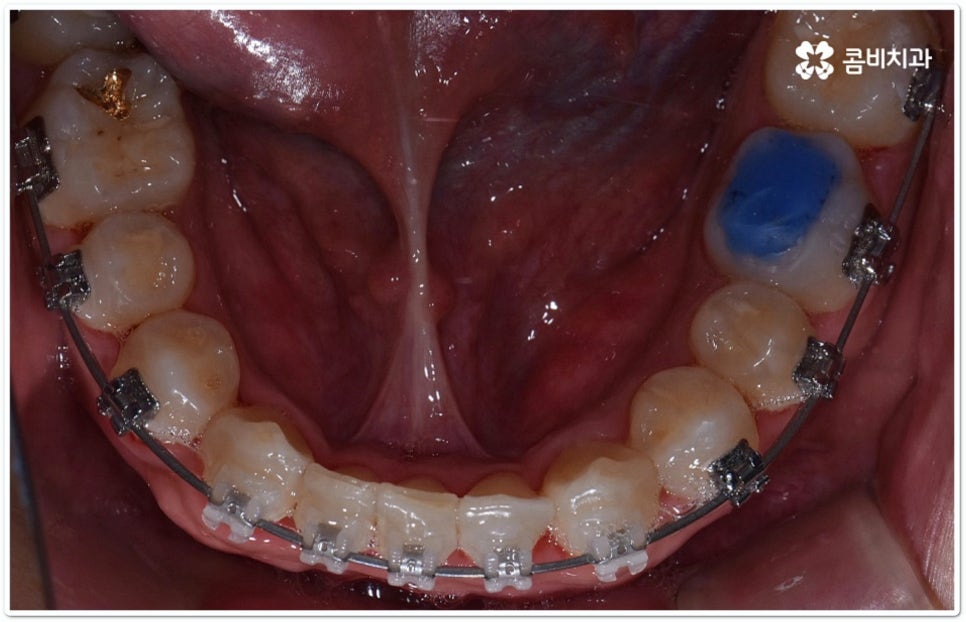

클리피씨교정 장치란 clippy-c 라는 단어 뜻에서 알 수 있듯이 클립이 달린 (clippy) 세라믹(ceramic) 브라켓 장치를 의미하고 있어요. 예전에 교정 장치에서 많이 쓰이던 방식은 고무줄 또는 미세철사를 이용하여 브라켓마다 각각 와이어를 묶어주는 것으로 날카롭게 잘린 철사 끝부분에 자칫 상처를 입을 수도 있고 한 달에 한 번 정도 치과에 내원하여 진행 상황에 따라 교정력을 조정하는 시간도 훨씬 더 많이 걸렸다고 할 수 있습니다.

이와는 다르게 클리피씨교정 장치는 자가결찰방식이라고 해서 각 브라켓에 여닫을 수 있는 특수한 클립(뚜껑)이 달려 있어 전체 와이어를 통과시켜 잡아주는 방식을 이용하기 때문에 겉면이 매끄럽고 진료 시간도 짧아지며 마찰로 빠져나가는 교정력을 줄여주어 좀 더 효율적으로 치아를 이동시킨다고 할 수 있어요. 즉 보다 적은 힘으로 지속적이고 부드러운 치아 이동을 가능하게 하므로 언급했던 것처럼 개인차가 있지만 전체 기간을 약 6개월 정도 단축시키고 치아가 이동할 때 느낄 수 있는 초기 통증도 감소시켜 줄 수 있는 거예요. 또한 치아 색상과 비슷한 세라믹 재질을 이용하기 때문에 음식을 먹거나 대화를 하는 등 입을 벌렸을 때 보일 수 있는 교정 장치가 그렇게 크게 눈에 띄지 않아 심미적으로도 뛰어나다는 장점을 가지고 있습니다.